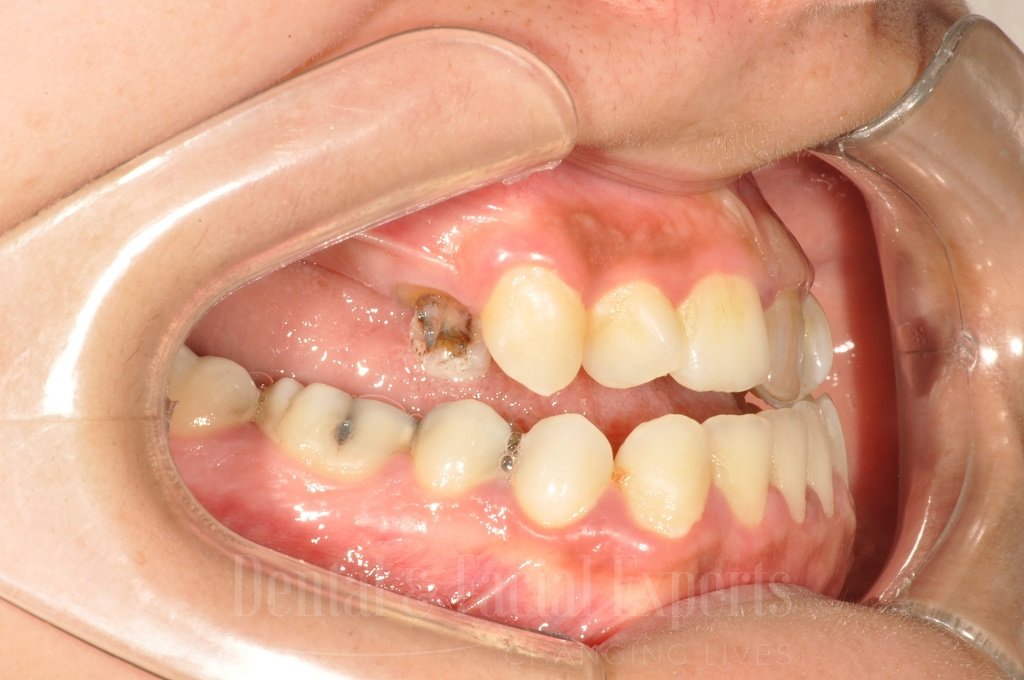

La cirugía maxilofacial es una especialidad médico-quirúrgica que aborda patologías, malformaciones y traumatismos de la cara, mandíbula, maxilares, boca y cuello. Su objetivo es restaurar la funcionalidad y mejorar la estética facial, abarcando procedimientos tanto reconstructivos como cosméticos.